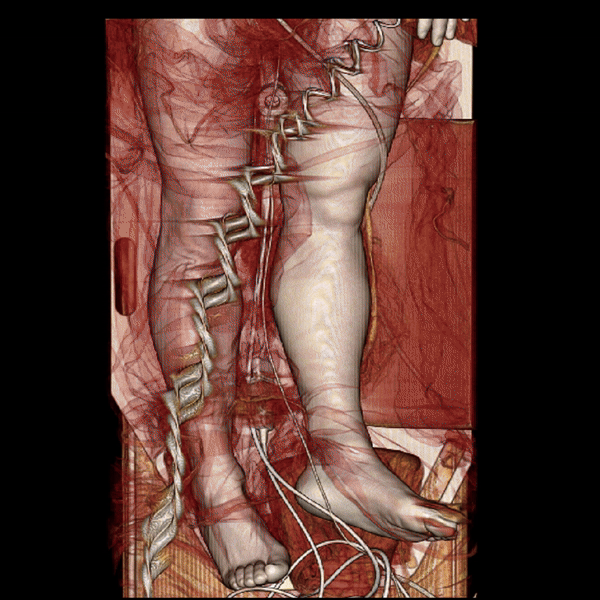

Figure B (Right): Rotational 3D reconstruction showing a brief view of the skin, muscle, and bone layers.